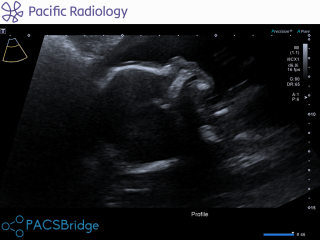

Hi i am 37 and pregnant with my second child. Had my bloods done at 20 weeks and anatomy scan also done scan was good but then today got call from midwife saying she got blood results and they have come bk high risk of down syndrome 1 in 140 chance. I now waiting hear from hospital what happens next for testing etc. I feel now distant to my pregnancy and now just super scared. Can any mums please help with advice as i so worried and a mess. Will this mean my child will have it etc. Attached is scan pic of our little girl. I am in nz